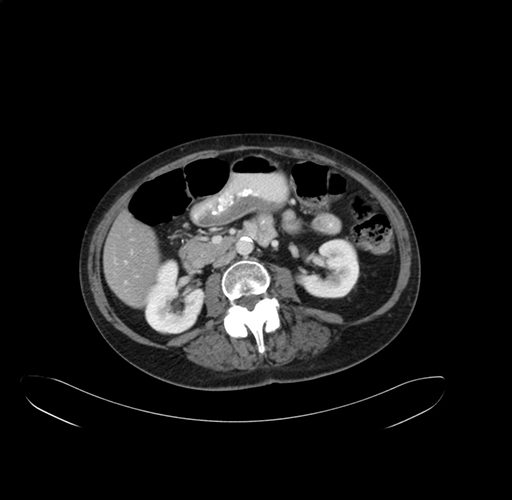

Pre-Chemo: Coronal Venous

Coronal Venous